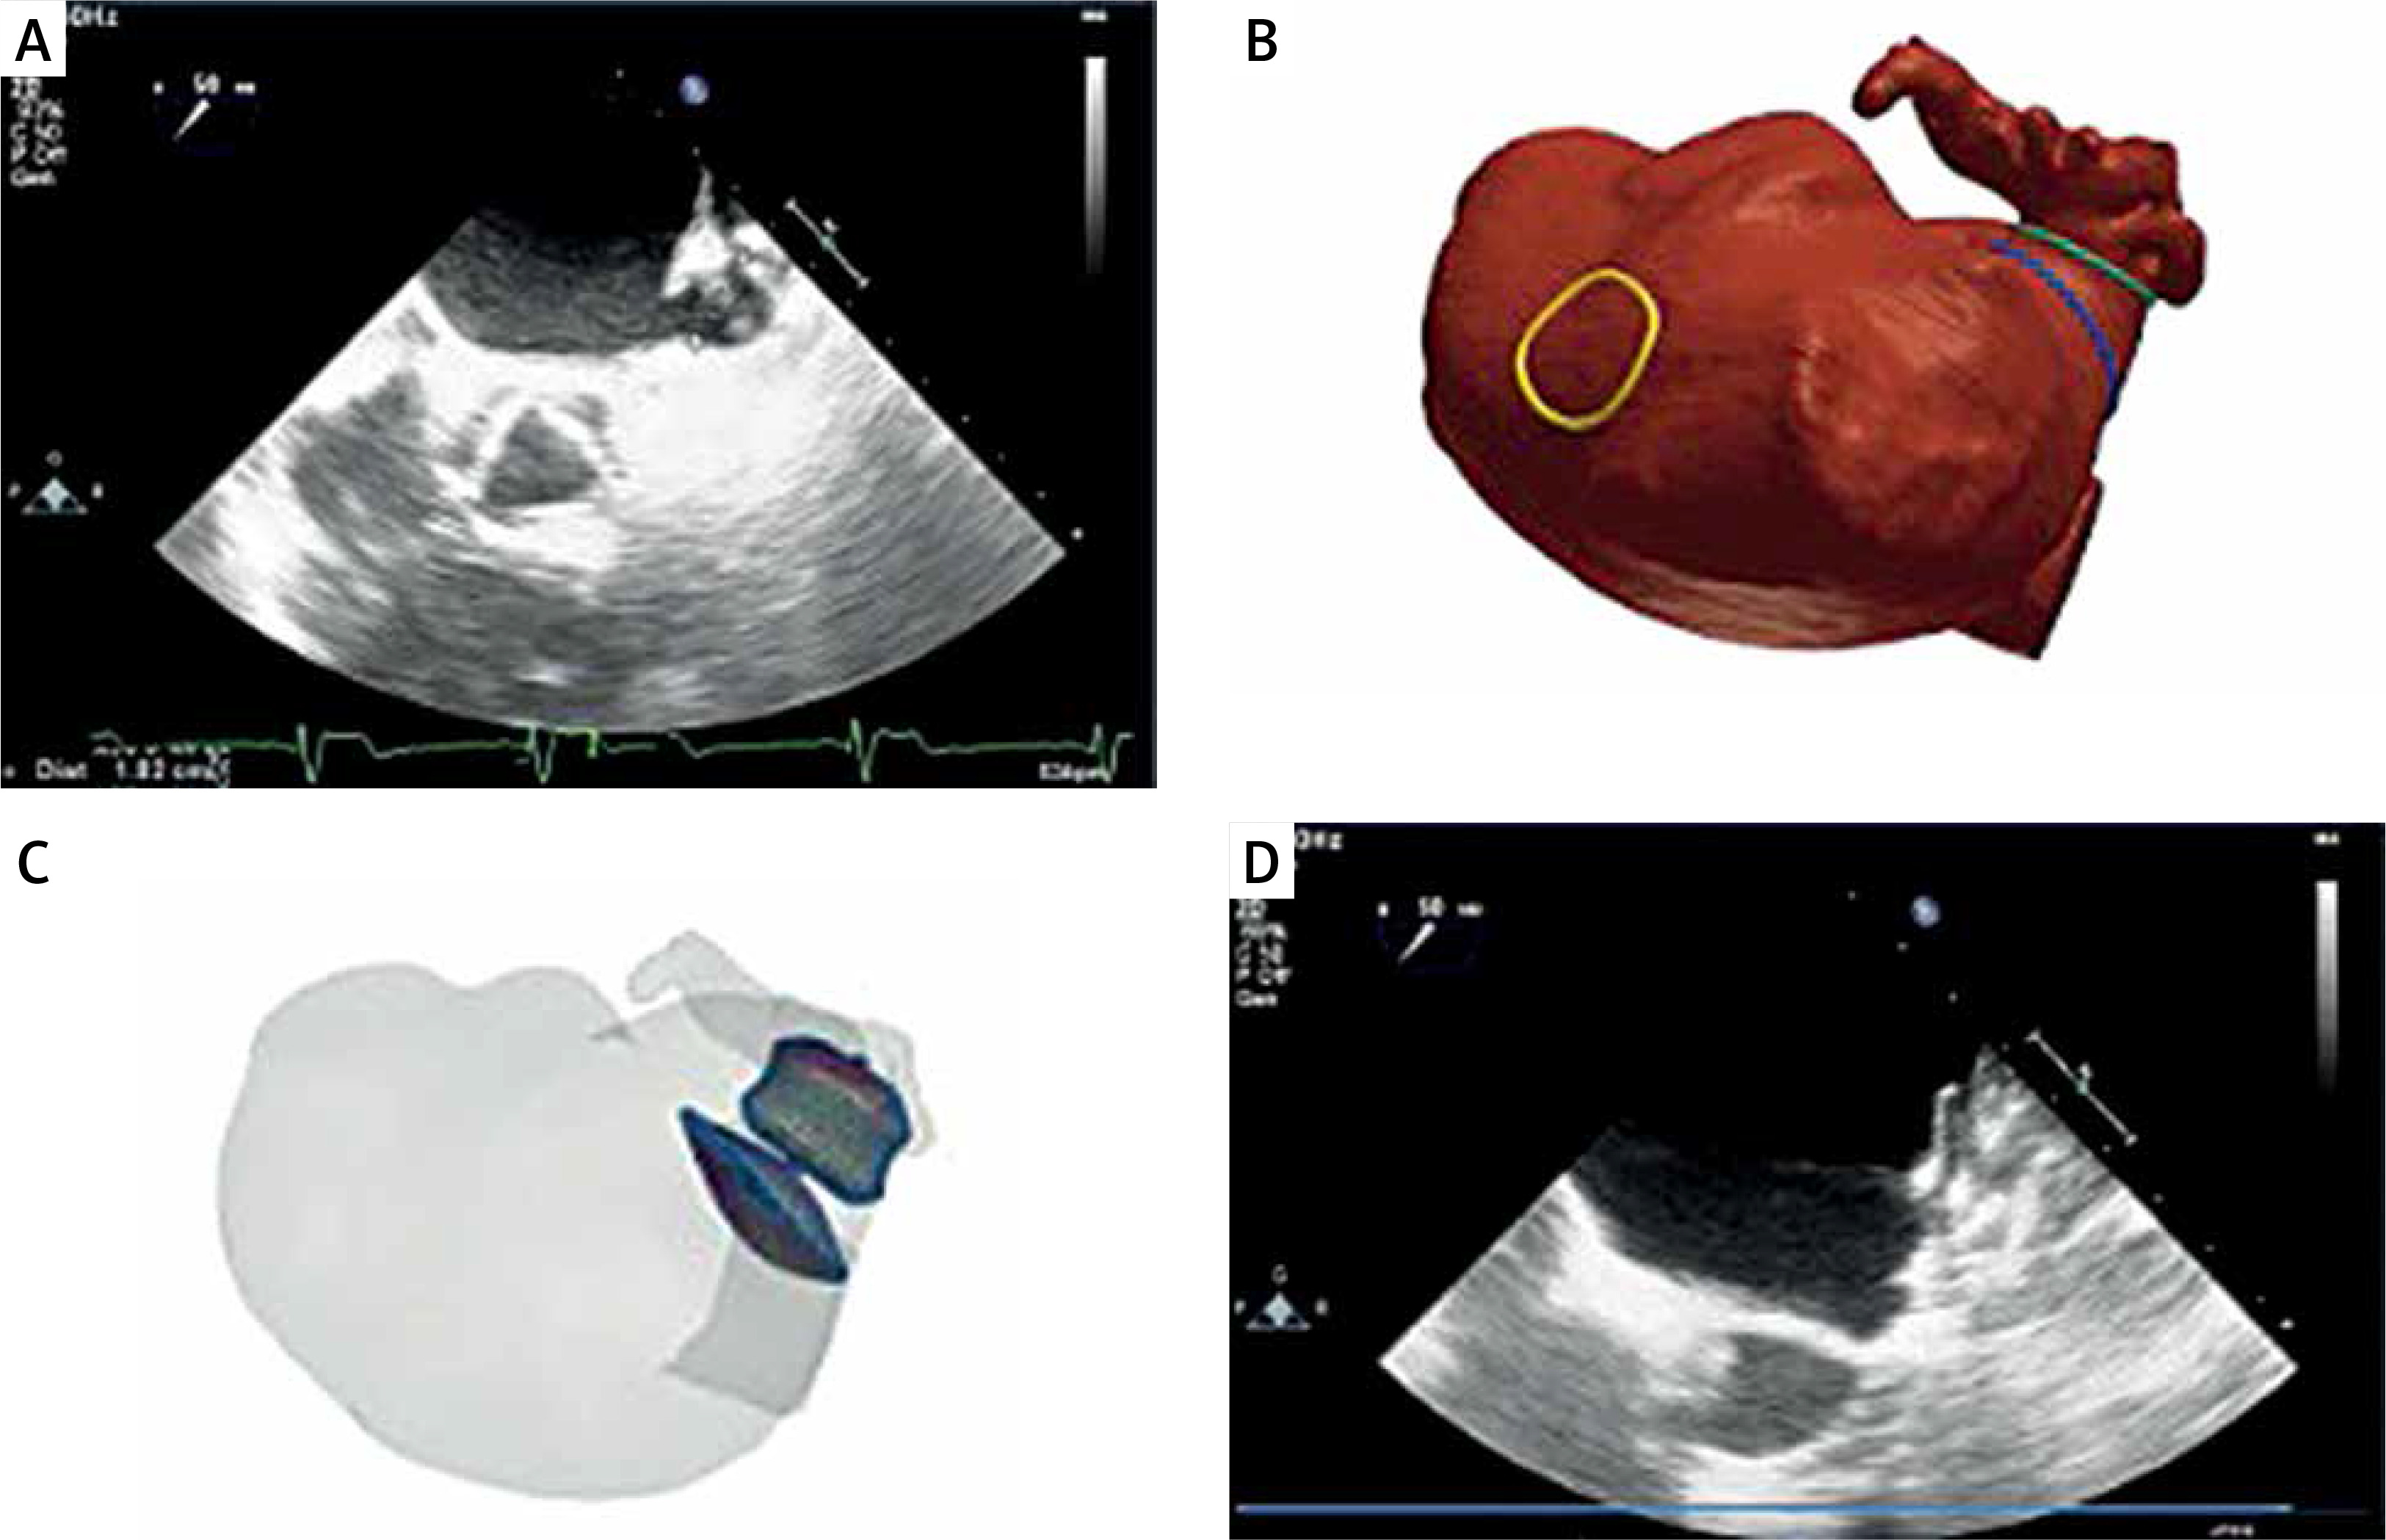

An 84-year-old man with persistent atrial fibrillation (CHA2DS2-VASc 6 points, HAS-BLED 4 points) was admitted for implantation of a left atrial occluder because of recurrent intestinal bleeding. Transthoracic echocardiography (TTE) revealed an enlarged left atrium with moderate valvular dysfunctions. In CT thrombus was excluded. Planning with FEops revealed a 2-lobed appendage with a very short but adequate landing zone (Figure 1). The AI simulated devices were the Amulet 22 mm, 25 mm, 28 mm, and 31 mm. According to our opinion and review of delivered simulations, taking into consideration frame deformation and the gap between the device and the wall of the appendage we chose a 25 mm device with high confidence for implantation. The stability was confirmed with a tug test. Proper placement of the device was confirmed in TTE on the next day, and in 2 months follow-up TEE. No complications were observed.

Figure 1

Combined visualization of the appendage using FEops and intraprocedural echocardiography. FEops clearly demonstrates 2-lobed structure (A) with short landing zone. Traditional intraprocedural echocardiography measured landing zone 2.29 cm (B) at the borderline of device sizes 25 and 28 mm. We chose the 25 mm device size based on our preassessment and FEops. The figure shows sample simulation for the 22 mm device with a clear gap in the red color and 25 mm with no gap and proper device deformation (C). We implanted the device with very good sealing (D) and positive follow-up